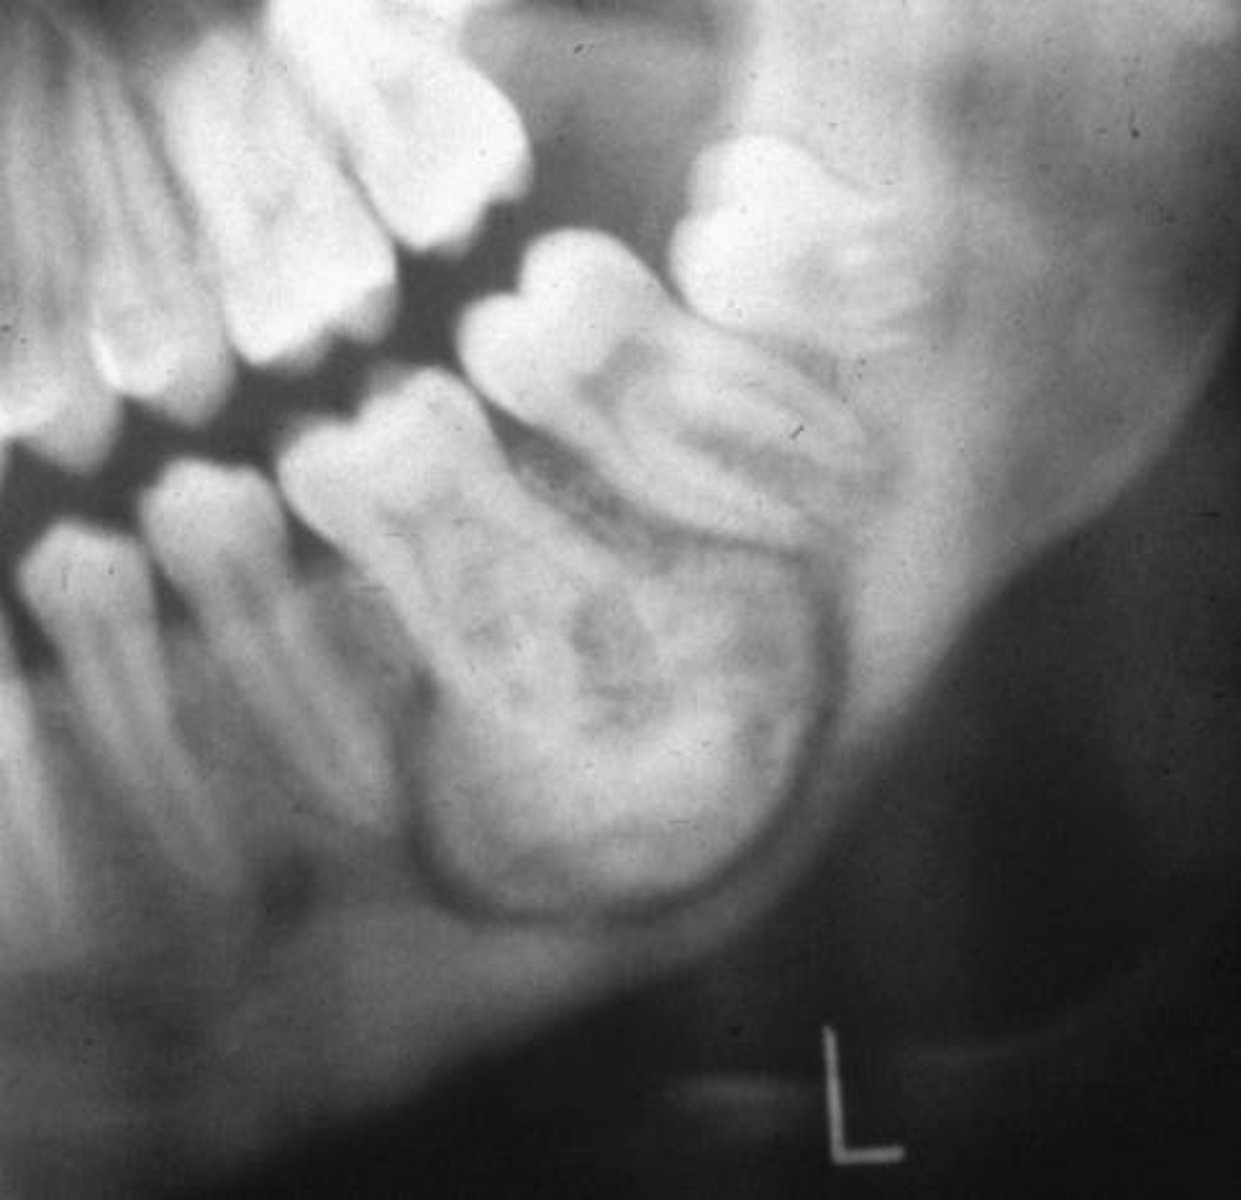

What is the radiographic appearance of compound odontomas?

cluster of miniature teeth (or extra mini tooth)

What are radiographic features of complex odontomas?

radiopaque mass